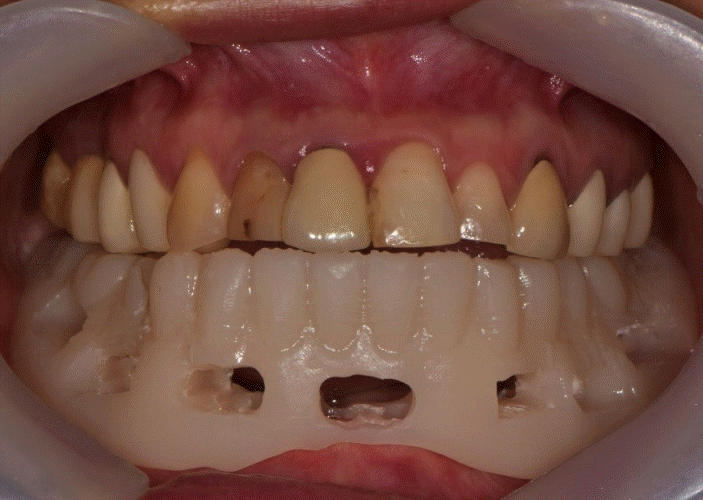

Fig. 12.

Intraoral scan with and without provisional restoration is taken. The occlusion and vertical dimension information is recorded for the final prosthesis.

본 증례는 44세 여환으로, 하악 의치가 계속 탈락하여 재제작을 원한다는 주소로 내원하였다. 상악은 고정성 수복물, 그리고 하악은 총의치를 착용 중이었고 하악 양측 구치부의 심한 골 흡수로 인해 유지력 소실로 불편감을 호소하였다. 3개월 전 하악 양측 견치를 발거한 이후로 하악 국소의치를 총의치로 전환하였고, 총의치는 구치부의 심한 교합면 마모와 의치의 후방부가 후구치 삼각 융기를 피개하지 않는 형태였다. 전신 병력으로는 지적장애 및 골관절염으로 약 2개월 간 약물 복용 중이었다. 상악 우측 제1대구치와 제2대구치, 제1소구치 그리고 제2소구치는 우식이 진행된 상태였고, 우측 제2소구치와 우측 제1대구치는 근관치료가 완료된 후 수복되지 않은 상태였다. 상악 좌측 제1소구치와 제2소구치, 그리고 제1대구치 수복물 하방으로 이차 우식이 진행된 상태였고, 전체적으로 교합평면이 균일하지 않은 형태였다(Figs. 1-3).상악 우측 구치부의 수복되지 않은 치아와 상악 좌측 보철물 하방의 이차 우식이 있는 치아는 모두 우식 제거가 필요하여 양측 구치부 각각 3개의 치아는 재수복을 결정하였고, 하악은 구치부의 심한 치조골 흡수로 인해 의치 사용은 불가할 것으로 판단하여 전방부에 임플란트를 식립하여 구치부는 캔틸레버 형태를 가지는 all-on-X 수복을 계획하였다. 의치의 수직고경에 맞춰 교합 평면을 균일하도록 하여 왁스업 시행하였고(Fig. 4), 이후 적절한 교합 수직 고경의 임시 의치를 제작하였다. 약 2개월의 적응기간을 거쳐 의치 적응도와 수직 교합 고경을 평가하였고 적절한 기능과 심미를 확인하였다. 상악 우측 제1소구치와 제2소구치, 제1대구치 그리고 상악 좌측 제1소구치와 제2소구치, 제1대구치는 우식을 제거한 다음, 임시 보철물로 재수복하여 적절한 교합 평면을 설정하였다(Fig. 5).환자가 적응한 임시 의치를 모델 스캔(Medit T710, Medit, Seoul, Korea)하여 프린팅용 레진(Graphy Tera Harz SG-100, Graphy, Seoul, Korea)을 이용하여 3D 프린팅하였고, 출력된 의치에 방사선 불투과성 레진(G-æenial Universal Flo, GC, Luzern, Swiss)을 부착하여 레진 마커를 형성하였다. 레진 마커를 부착한 프린팅 의치를 장착한 채로 콘빔 전산화 단층촬영(CBCT, R2 Studio Q, Megagen, Seoul, Korea)를 촬영하였다(Fig. 6). 촬영한 CBCT 데이터와 의치 스캔 파일을 중첩하여 CAD 소프트웨어(R2 Studio Q, Megagen, Seoul)를 통해 이상적인 임플란트 식립을 계획하였다. 전후방 거리를 연장하여 적절한 캔틸레버를 부여하기 위해 전방부에 3개의 임플란트를 식립하고, 양측 후방부에는 약 30도 경사진 임플란트를 식립하도록 계획하였다(Fig. 7).가이드는 상악의 자연 치열과 대합되는 의치 복제 형태의 상부 가이드, 그리고 가이드 핀이 존재하는 하부 가이드로 이루어지도록 디자인되었다(Fig. 8). 상부 가이드는 임시 의치의 스캔 데이터를 이용해 상부 가이드의 하부면과 하부 가이드의 상부면이 장착되어 구내에서 적합될 수 있도록 CAD 소프트웨어(Meshmixer, Autodesk, San Francisco, CA, USA) 상에서 디자인되었다. 임시 의치의 하부면과 하부가이드의 하부면을 치은과 중첩시켜 어버트먼트의 위치에 홀을 형성한 다음 3D 프린팅(Graphy Tera Harz SG-100, Graphy, Seoul, Korea) 하였다. 수술 당일 장착될 임시 보철물 또한 동일한 CAD 소프트웨어를 통해 제작하였다.수술 당일 이중 가이드를 구내에 장착하여 하부가이드를 고정 핀으로 고정시킨 후(Fig. 9), 계획된 위치에 임플란트 고정체를 식립하였다. 임플란트는 5개 모두 외부 연결형 고정체(AnyOne External, Megagen, Seoul, Korea)를 사용하였고, 식립 시 식립 토크는 모두 40N 이상, ISQ는 70이상으로 양호한 초기 고정력을 확보하였다(Fig. 10). 즉시 부하를 위해 기성 어버트먼트를 체결하였고, 임시 보철물을 장착하여 양측 소구치부에서의 균일한 교합을 확인하였다(Fig. 11).임플란트 주위 골과 치은의 회복을 위해 약 2달간 임시 보철물을 경과 관찰하였고, 이후 최종 보철을 위한 인상 채득을 시행하였다. 상하악 임시 보철물을 장착한 중심교합 상태에서 구내 스캔(Trios 4, 3 Shape, Copenhagen, Denmark)을 시행하여 악간 관계를 채득하였다(Fig. 12). 임시 보철물을 제거한 상태에서 하악의 전방부 3개의 임플란트에 scan body(Scan Abutment, Megagen, Seoul, Korea)를 연결하고, 양측 최후방 임플란트 2개에는 각각 Ti base multi-unit abutment(multi-angled abutment, Osstem, Seoul, South of Korea)를 30Ncm으로 체결한 후 multi scan body(TS Multi scanbody, Osstem, Seoul, Korea)를 연결하여 구내 스캔(Trios 4, 3Shape, Copenhagen, Denmark)을 시행하였다. 이후 스캔 바디를 연결하여 채득한 스캔 파일을 상하악 임시 보철물 상태에서 채득한 스캔 파일과 중첩하여 CAD 소프트웨어(exocad GmbH, Darmstadt, Germany)에서 최종 보철물을 디자인하였다(Fig. 13).최종 보철물은 양측 최후방 임플란트 고정체에 각각 Ti-base(TS multi Ti base, Osstem, Seoul, Korea)와 접착된 나사 유지형 단일 지르코니아 크라운으로, 지르코니아 블록(Zircen, Kuwotech, Gwangju, Korea)을 밀링하여 제작하였고, 치경부 하방으로 포세린으로 치은 형태를 부여하였다. 전방부 3개의 임플란트 고정체에는 맞춤형 지대주를 제작하여 30N으로 체결하였고, 양측 최후방 고정체는 20Ncm으로 체결한 후 레진 시멘트(Rely X U200; 3M ESPE, St. Paul, MN, USA)로 접착 시행하였다. 장착 후 중심교합시 양측의 제1대구치 부위에서 교합력이 적게 가해지도록 교합 조정 시행하였으며, 전방과 측방운동시에 임플란트 상호보호교합이 되도록 조정하였다. 또한 연결부 하방으로 치실을 통과시켜 치은 점막 사이 공간을 평가하였으며, 구강 위생 관리의 용이성을 확인하였다. 이후 1주, 1개월, 3개월 경과 관찰하였고, 환자는 저작이나 심미, 발음 등에서 만족해하였다(Figs. 14 and 15).